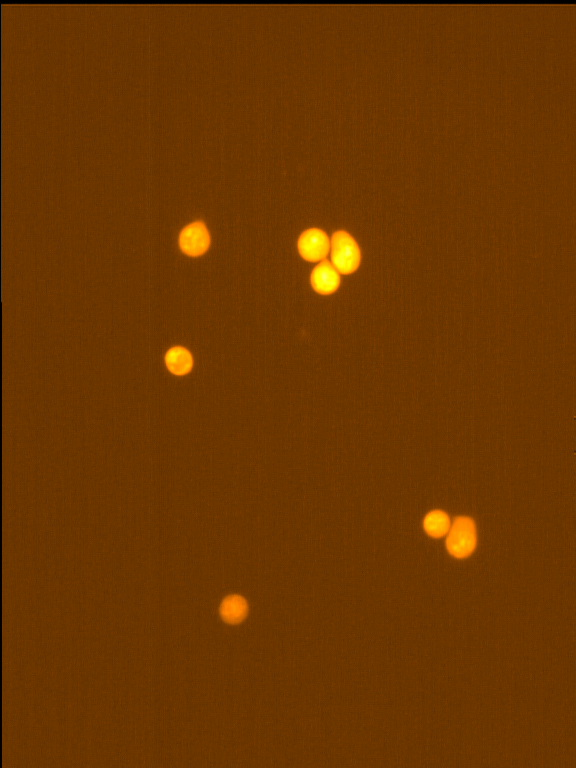

Fig. 4 through 6 show the morphological features of Raji cell sub-lines exposed to DOX, indomethacin, or verapamil. Some of the reversal agents significantly increased the frequency of apoptotic cells compared with control cells. Thus, the P-gp reversal agents were able to overcome apoptotic resistance in the NHL cell-line model. Apoptotic cells in the controls contributed approximately 10% of the whole population (i. e., 61/600 x 100 = 10.16% for TK+ and 69/600 x 100 = 11.5% for TK-). After exposure to the P-gp reversal agents, apoptic cells increased to 22.3% with indomethacin and to 43% with doxorubicin in TK+ cells. In TK- cells, apoptic cells increased from 11.5% to 26.8% and 75.7% with indomethacin and doxorubicin, respectively.

Fig. 6: Morphological features of Raji TK- cells after treatment with indomethacin (1), verapamil (2), and DOX (3). In each row, left images show intact cells, middle images show apoptotic cells, and right images show necrotic cells as they appeared under the microscope X 200